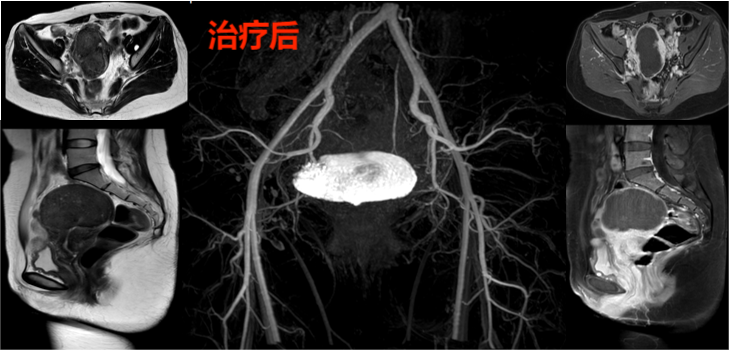

通过磁共振检查与妇检病理排除其他恶性疾病,胡女士适合进行介入微创栓塞保留子宫的治疗方法治疗,经过右腿打针超选择栓塞子宫腺肌症的营养血管,胡女士的子宫腺肌症血供丰富、生长旺盛,双侧子宫动脉供血(如下图)。

治疗过后3个月来例假,月经量很少,胡女士发现痛经消失了,胡女士不敢相信困扰她多年的痛经竟然这样消失了,她还有些不敢相信。虽然出院时韦文姜副主任医师告诉她治疗后三个月复查,但胡女士想再观察几个例假周期看看痛经是不是真的好了。这样一观察就1年多,痛经和呕吐没有再出现,治疗后16个月胡女士回门诊复查磁共振显示:子宫腺肌病病灶坏死无强化,较治疗前病灶明显缩小(如下图)。